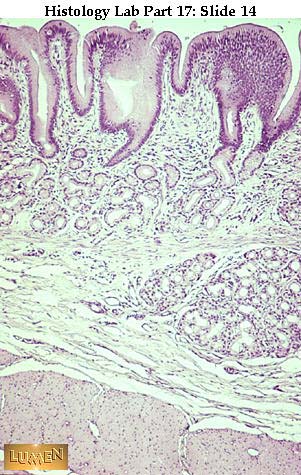

What part of the GI Tract is this?

Pylorus (just before duodenum)